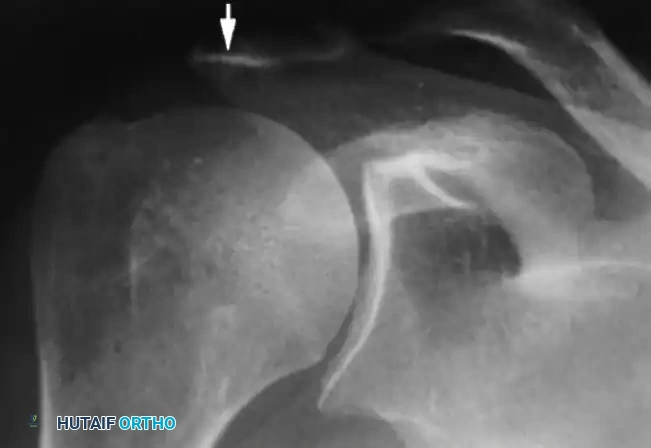

Radiographic Hallmarks

Standard radiographic evaluation must include a true anteroposterior (Grashey), scapular Y, and axillary lateral view. The classic radiographic findings of a chronic massive rotator cuff tear progressing to arthropathy include:

1. Superior Migration: An acromiohumeral interval (AHI) of less than 7 mm.

2. Loss of Joint Space: Progressive narrowing of the glenohumeral articulation.

3. Humeral Head Osteophytes: Inferior osteophyte formation due to altered loading.

4. The "Sourcil Sign": Sclerosis and erosion of the inferior acromial surface as the humeral head chronically "articulates" against the undersurface of the acromion.

Image